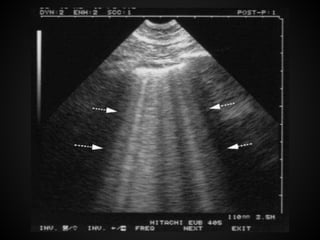

A lines are horizontal, regularly spaced

hyper-echogenic lines representing

reverberations of the pleural line. These

are motionless and are artifacts of

repetition.

B lines are vertical narrow lines arising

from the pleural line to the edge of the

ultrasound screen. ‘‘comet tails ’’